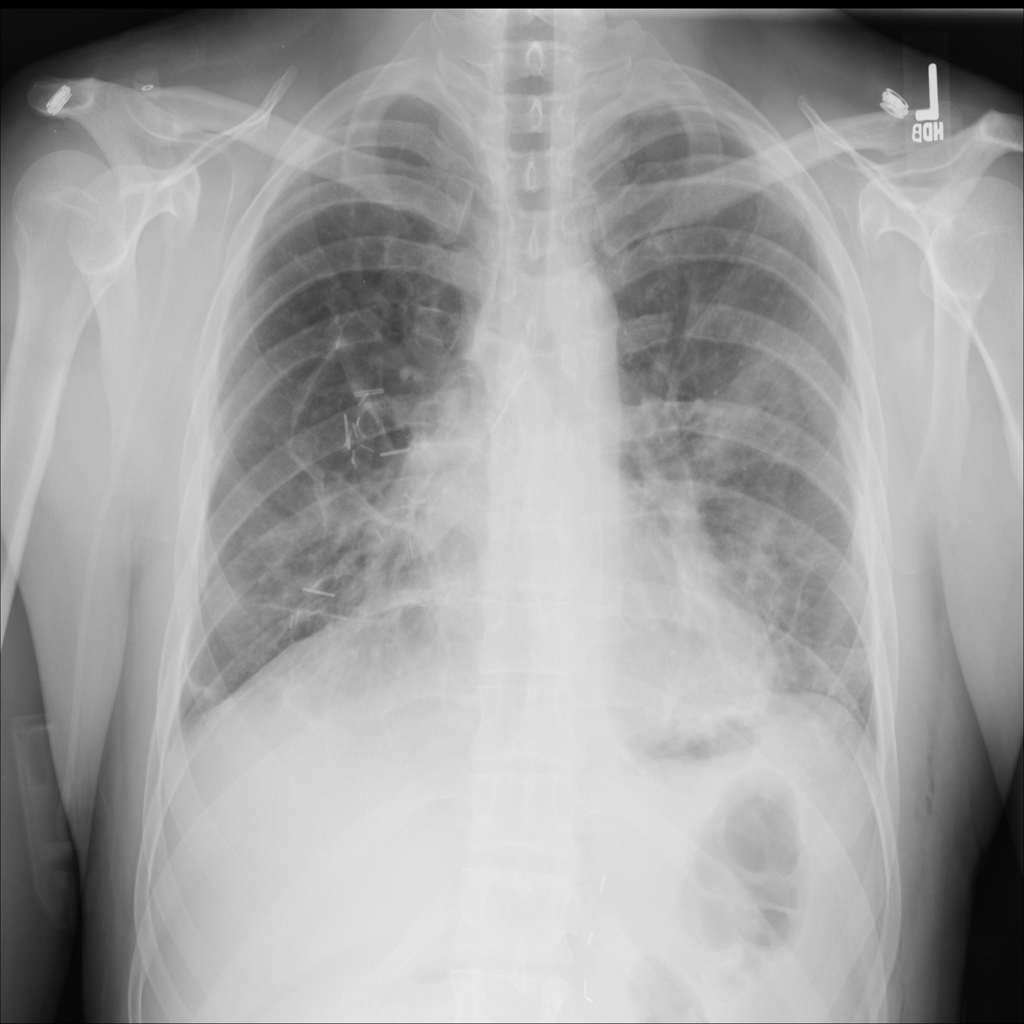

PAT-0E82 · IMG-000Emphysema

PAT-0E82 · IMG-000

AP